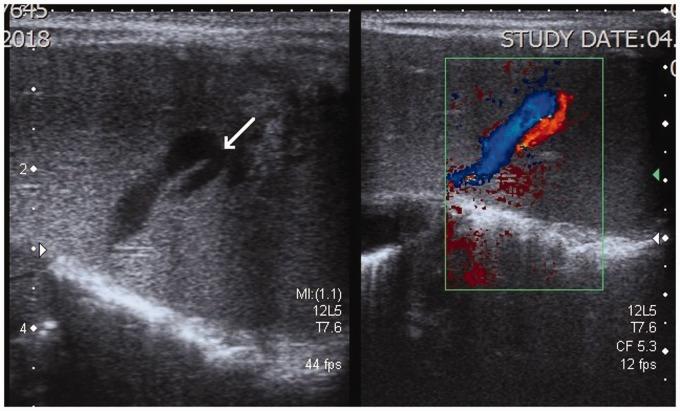

Intrahepatic congenital portosystemic venous shunts are rare vascular anomalies. We report a unique case of a neonate with an intrahepatic congenital portosystemic venous shunt with concurrent congenital duodenal web. Such association has not been previously reported to our knowledge. Interestingly, the shunt became apparent on the seventh day, after a delayed start of oral feeding due to the neonate's recovery from the duodenal web surgery. The shunt was small and the clinical symptomatology mild. No direct treatment was required. The laboratory and the ultrasound follow-up of the child noted a spontaneous resolution of the shunt by the age of six months.

肝内先天性门体静脉分流是罕见的血管异常。我们报告了一例独特的新生儿病例,该新生儿患有肝内先天性门体静脉分流并伴有先天性十二指肠蹼。据我们所知,此前尚未有这种关联的报道。有趣的是,由于新生儿从十二指肠蹼手术中恢复,经口喂养开始延迟,分流在第七天变得明显。分流较小,临床症状轻微。无需直接治疗。对该患儿的实验室检查和超声随访发现,分流在六个月大时自行消退。